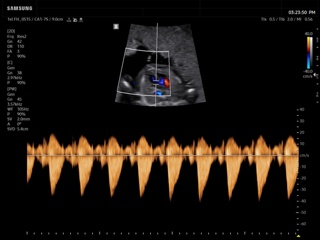

In the section "Оbsterics" of atlas the results of ultrasonic examinations of pregnant women with different durations of gestation are represented. Here you can see images of internally organs, cerebrum, cordis and the sex of the fetus, the sonograms of multiple pregnancy, the blood flow in placenta and umbilical cord, defects of fetal`s development, etc.